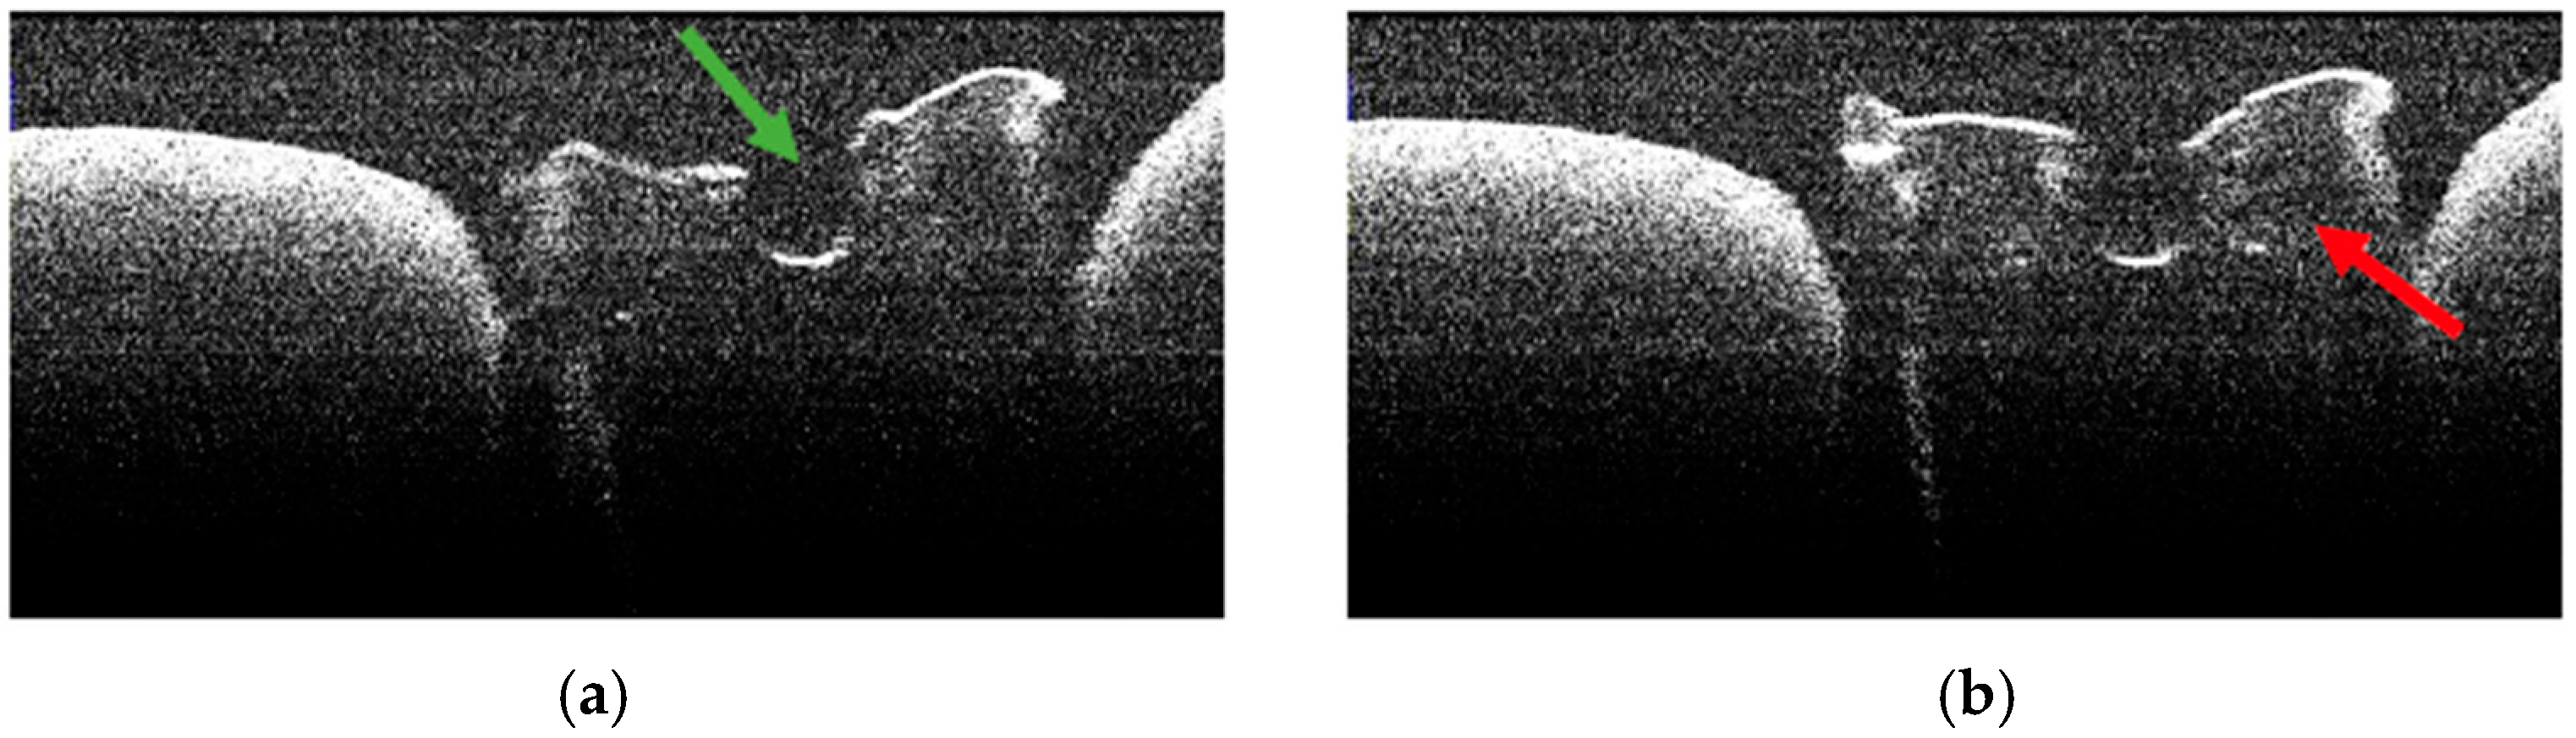

3.5. OCT Examination of Specimens from Group B

3.6. Topographic Distribution